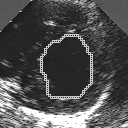

In this work, we present a new method to shape-based segmentation of deformable anatomical structures in medical images and validate this approach by detecting and tracking the endocardial border in an echographic image sequence. To this end, a global prior knowledge of the endocardial contour is captured by a prototype template with a set of admissible deformations to take into account its inherent natural variability over time. In this approach, the data likelihood model rely on an accurate statistical modeling of the grey level distribution of each class present in the image. The parameters of this distribution mixture are given by a preliminary estimation step which takes into account the distribution shape of each class. Then the tracking problem is stated in a Bayesian framework where it ends up as an optimization problem. This one is then efficiently solved by a genetic algorithm combined with a steepest ascent procedure. This technique has been successfully applied on synthetic images and on a real echocardiographic image sequence. This method seems to be particularly well suited to handle ultrasound images with strong speckle noise on which edge information cannot be exploited. Finally, the local and global minimization procedure we propose is fast, robust and do not require initialization of the template close to the desired solution. Initialization may be defined at random, leading to segmentation and tracking procedure that are completely data driven. (slides)

Figure 1:   Tracking of the endocardial contour in a medical echographic sequence at different time frames during the cardiac cycle. From top left to bottom right : frame 1, 4, 6, 9, 12, 13, 18, 20, 27, 30, 35, 40, 41, 44, 46.